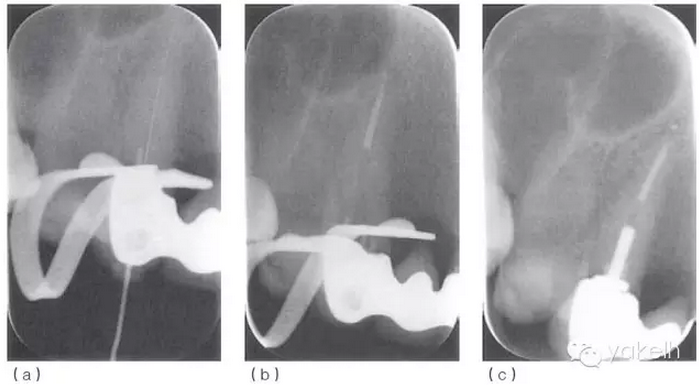

¤¤口外檢查可見右頰中度腫脹,右側鼻唇溝消失??趦葯z查可見牙列中有部分修復體。13腭側可見窩洞暫封,唇側近頸部黏膜可見一處潰瘍,10mm×15mm(圖 5.2.1a),其他軟組織正常。13對EPT和溫度測試無反應,叩痛,根尖X線片(圖 5.2.1b)顯示根尖周透射影。

圖 5.2.1(a)次氯酸鈉意外進入根尖周組織24小時之內,引起潰瘍。(b)13術前X線片。

¤¤使用根尖定位儀確定根管的工作長度,拍攝X線片(圖 5.2.2a)加以驗證。采用化學-機械方法進行完善的根管預備后,使用牙膠和根管封閉劑,采用熱垂直加壓技術進行根管充填(圖5.2.2b,c)。1個月后復診,患者無癥狀,潰瘍變小,僅黏膜表面遺留瘢痕(圖 5.2.3)。

圖 5.2.2(a)13確定工作長度的X線片。(b)13根管充填中X線片。(c)13根管充填后X線片。